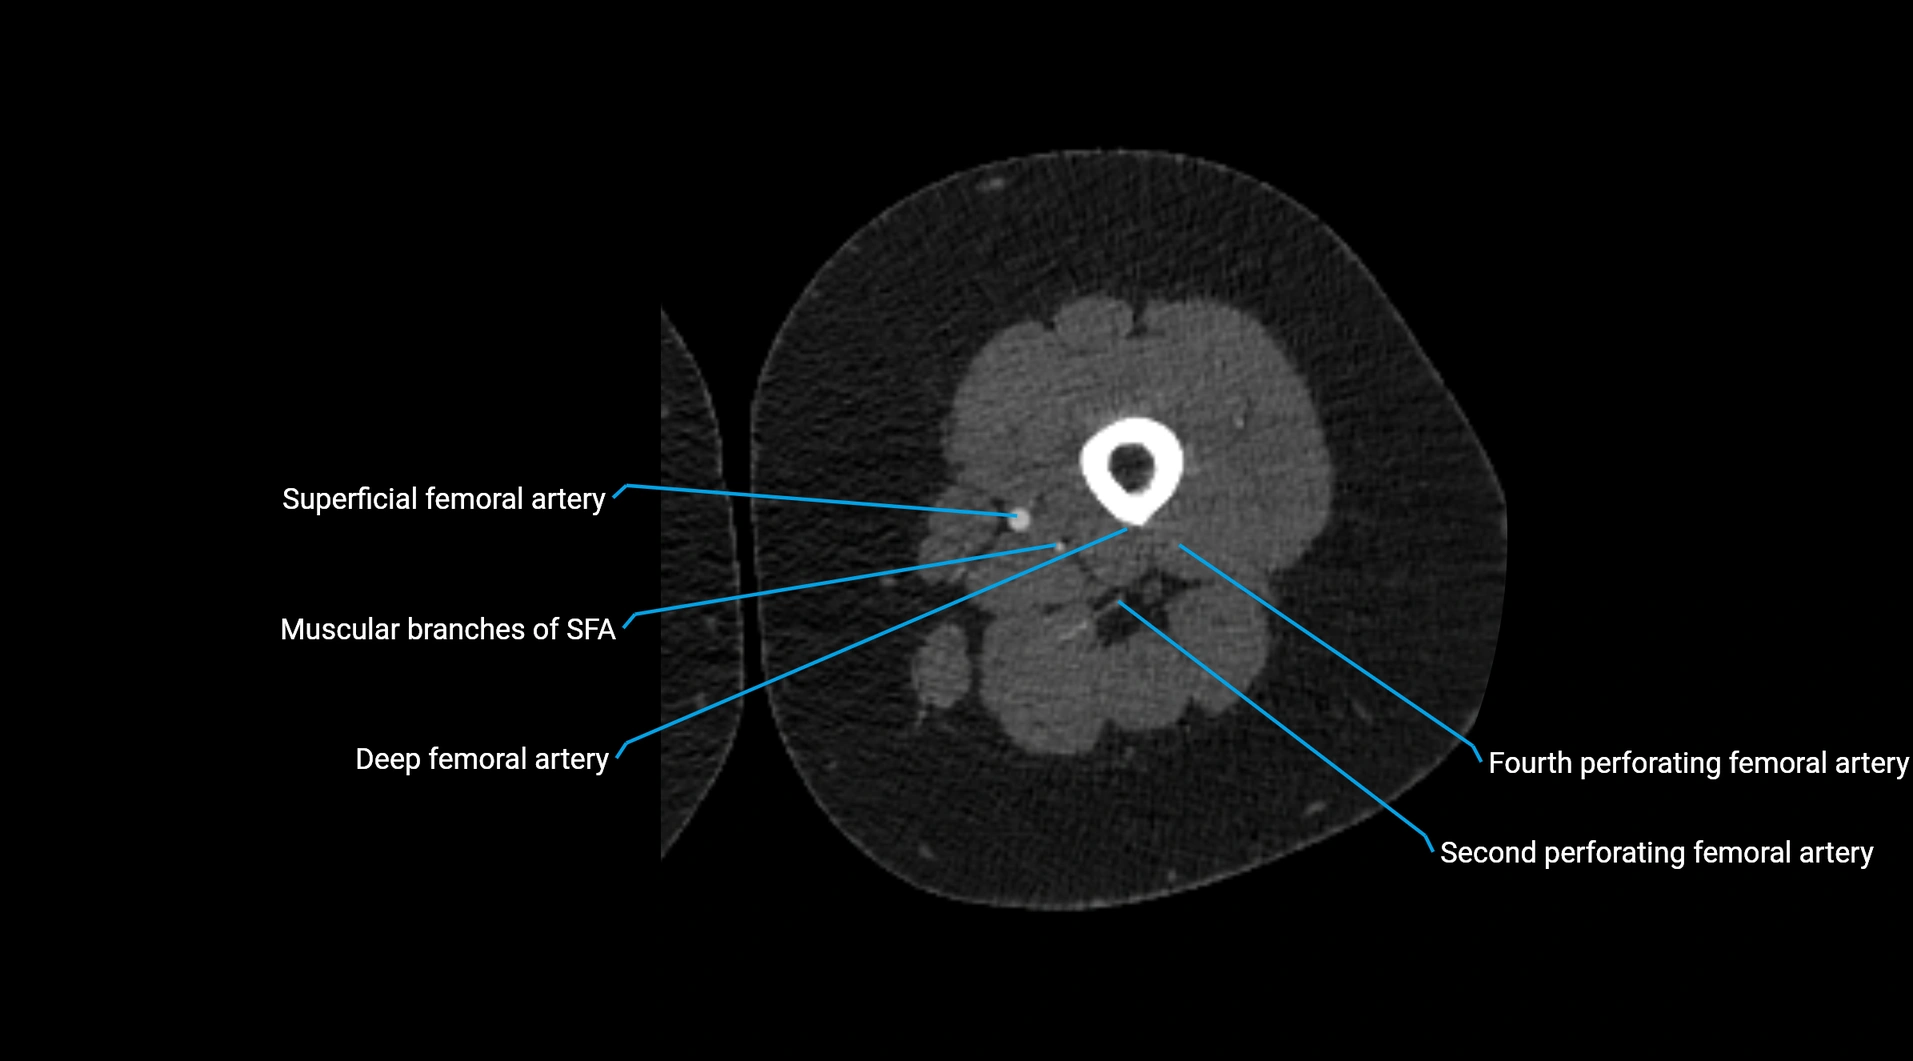

Contrast-enhanced CT (CTA):

• Gold standard for abdominal aortic imaging

• Provides excellent detail of lumen, wall, aneurysm, thrombus, and branch vessels

• Multiplanar and 3D reconstructions help in aneurysm measurement, stent graft planning, and dissection evaluation